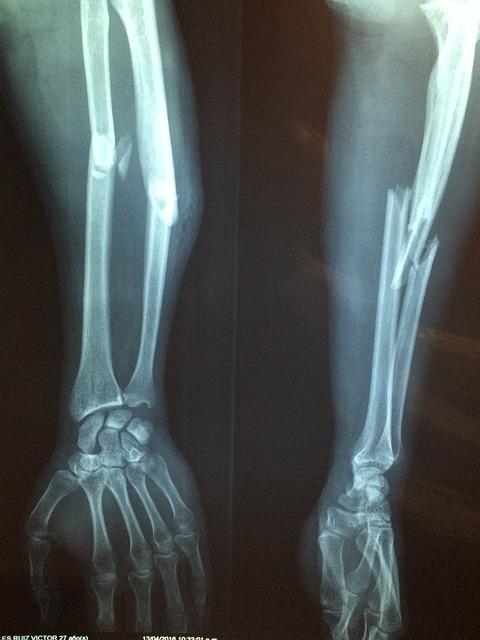

3) 잦은 골절

특히 엉덩이, 손목, 척추의 뼈는 사소한 넘어짐이나 약간의 충격에도 쉽게 부러질 수 있습니다.